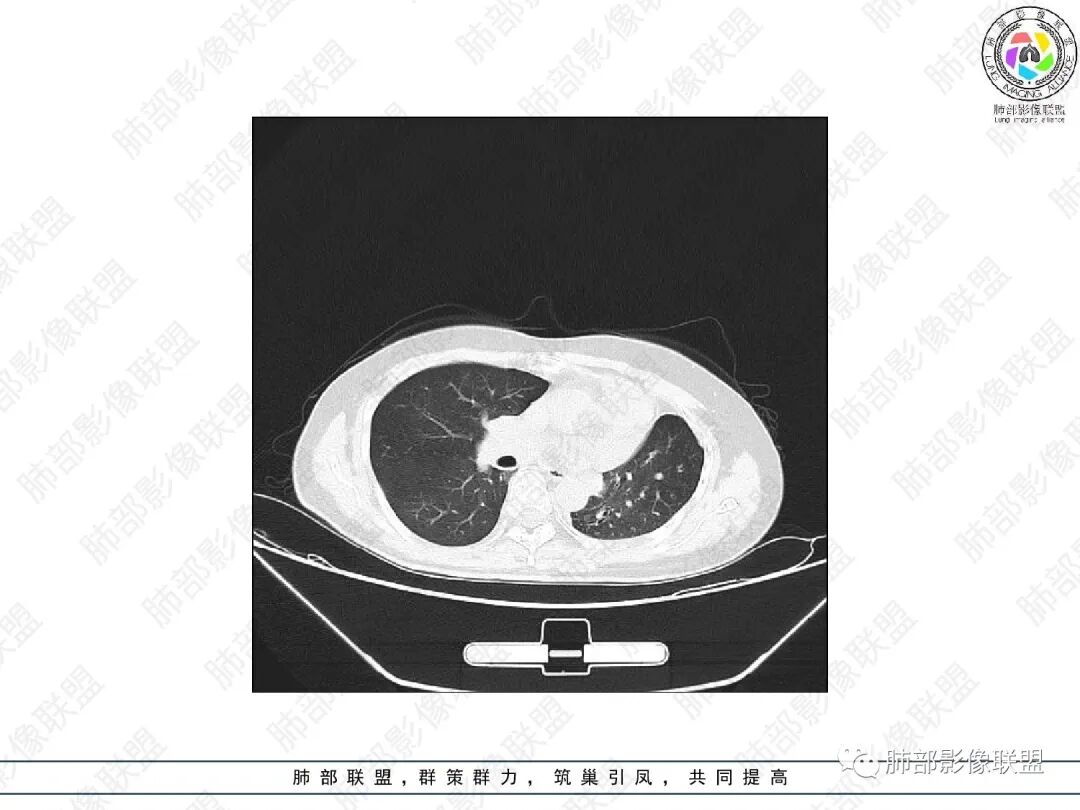

1.中年女性,主因“咳嗽、咳痰半年余”入院,既往史:8年前因左肺病在外院变行左肺叶切除术,诉术后抗结核治疗1年,具体病理等不详。实验室IGE显著增高。

2.胸部CT:右肺上叶及中叶不规则块状影,沿支气管走行方向指套样影,支气阻塞湖嵌塞,腔内可见高密度影。灶周可见磨玻璃,外围见结节影及树芽征。左肺体积缩小,见不规则条索影、胸膜增厚,纵隔牵拉左移。

3.综合分析:结合患者病史及胸部CT主要鉴别ABPA(右肺上叶不规则块影,指套样顺延支气管方向,抗结核治疗1年,肺部病灶仍明显)及继发性肺结核TB(右肺上叶不规则肿块,其可见高密影,边缘模糊,周围卫星灶、树芽征,沿支气管爬行)。

完善气管镜及病理、检验结果(IgE显著增高)等支持ABPA诊断。且给予激素及伊曲康唑治疗后复查胸部CT提示病灶较前吸收,所以诊断明确。